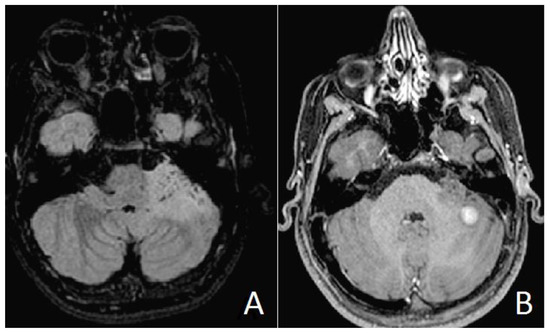

2. Case Presentation (Material)

2.2. Results